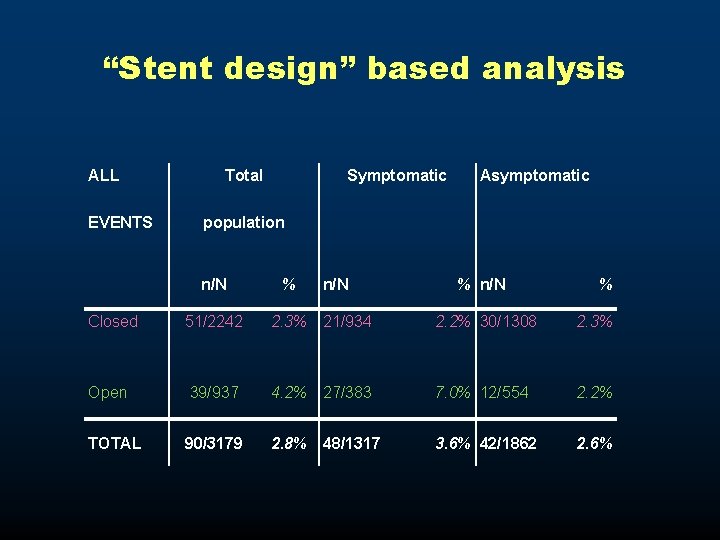

“Stent design” based analysis ALL EVENTS Total Symptomatic Asymptomatic population n/N % Closed 51/2242 2. 3% 21/934 2. 2% 30/1308 2. 3% Open 39/937 4. 2% 27/383 7. 0% 12/554 2. 2% TOTAL 90/3179 2. 8% 48/1317 3. 6% 42/1862 2. 6%

“Stent design” based analysis All events: open vs. < closed cell Odds Ratio 95% C. I. Total population 1. 876 [1. 227 -2. 868] Symptomatic population 3. 297 [1. 840 -5. 908] Asymptomatic population 0. 943 [0. 479 -1. 856]

“Stent design” based analysis LATE EVENTS Total Symptomatic Asymptomatic population n/N % Closed 29/2242 1. 3% 12/934 1. 3% 17/1308 1. 3% Open 32/937 3. 4% 24/383 6. 3% 8/554 1. 4% TOTAL 61/3179 1. 9% 36/1317 2. 7% 25/1862 1. 3%